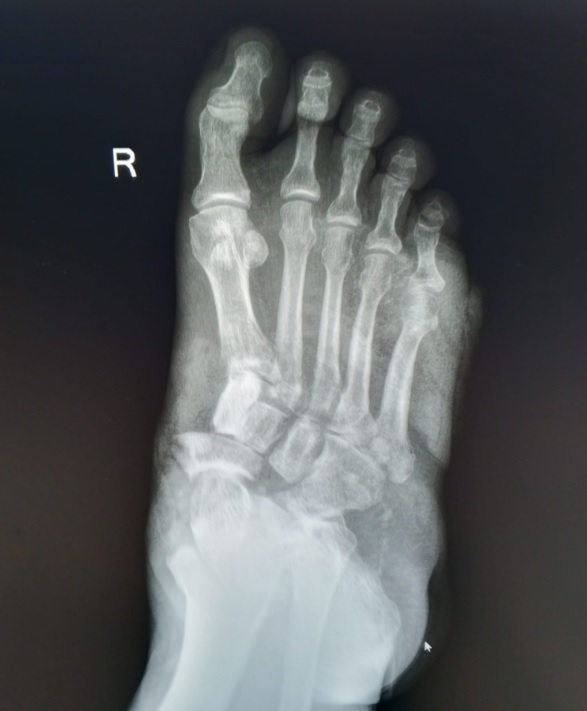

- Röntgen: Ayak ve ayak bileğinde kemik kırıkları, eklem boşluğu daralmaları ve deformiteleri gösterebilir.